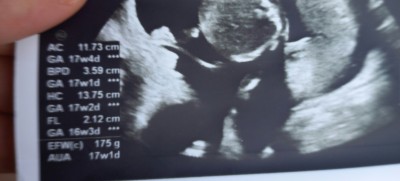

Uktrasyonda bebegin boyu ve kilosu nerede yazıyor acaba resimli

Gebelik haftası

17+1

boy

kilosu

bakarmısiniz

Fl yazanı 7 ile çarpınca bebeğin baş popo mesafesi çıkıyor canım. 175 gram da kilosu

Ultrason da FL yazan değer ile 7 yi çarparsan bulursun canım